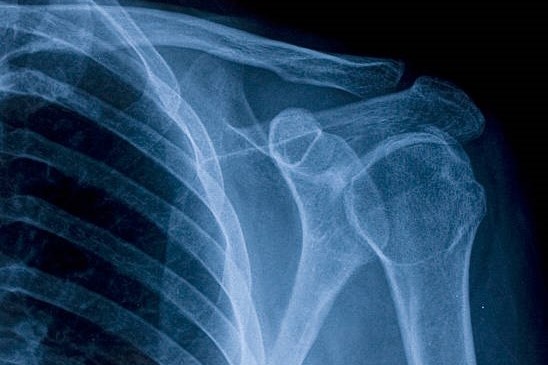

Röntgendiagnostik

Wir fertigen Röntgenbilder mittels moderner digitaler Röntgentechnik an.

Details zur Röntgendiagnostik

- Wir fertigen Bilder des Skeletts an bei Verdacht auf einen Knochenbruch.

- Wir führen Verlaufskontrollen nach Operationen eines Knochenbruchs oder bei der Behandlung von Knöchenbrüchen ohne Operation durch.

- Wir führen die regelmäßigen Kontrollen nach der Implantation von künstlichen Gelenken durch.